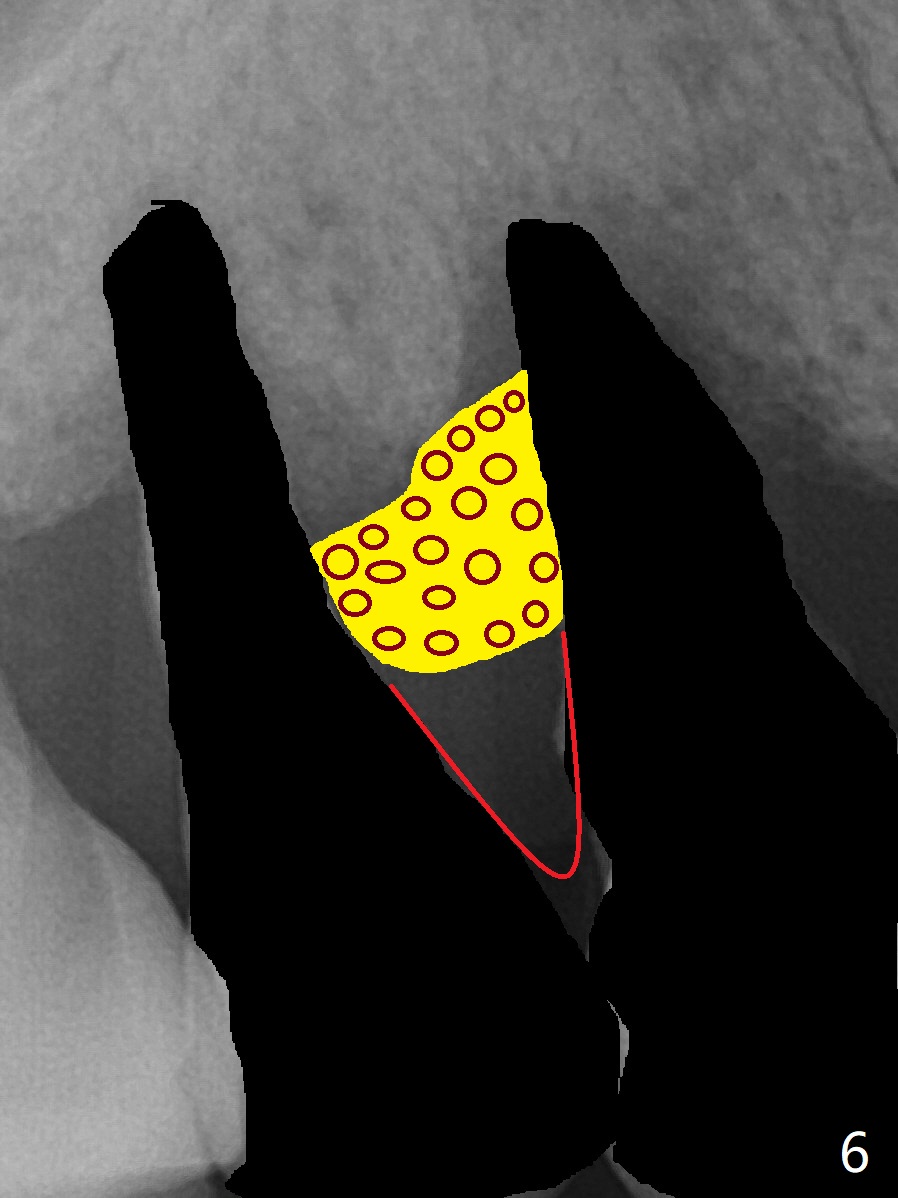

图三红线代表龈乳头,当两个邻牙拔除后,没有特殊处理,龈乳头不可避免收缩(图四)。如何预防呢?拔除4时,发现牙槽窝肉芽组织延申到牙槽嵴与乳头之间(图五:黄色)。刮治肉芽组织后,在空缺处,填入粘性骨粉(图六:圆圈),应该能够减少术后龈乳头萎缩。